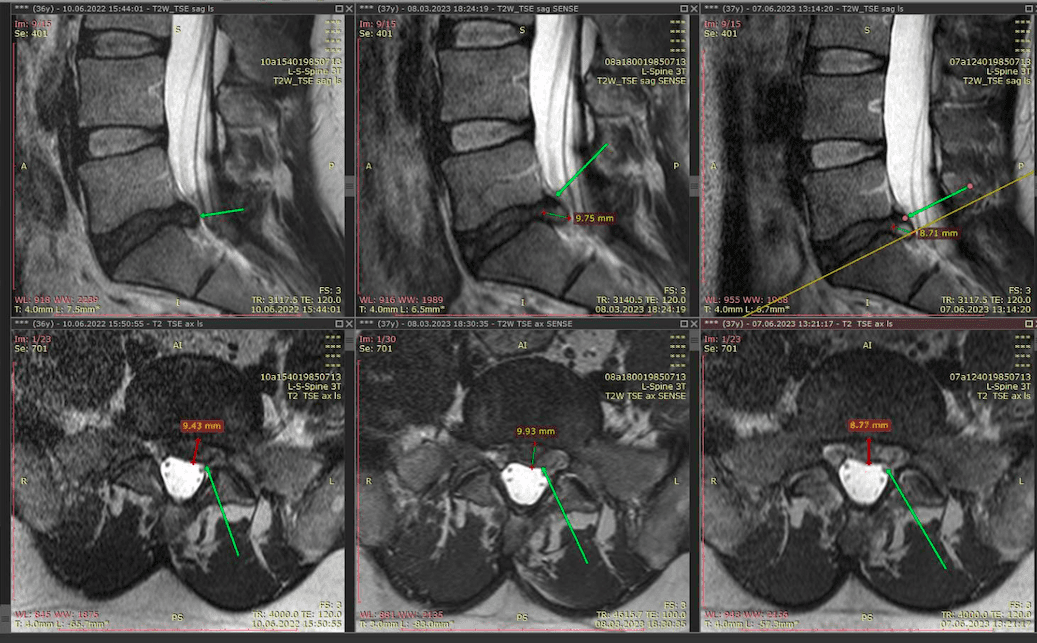

Метод лікування грижі шляхом стимуляції резорбції в Україні був впроваджений у 2020-2021 роках.  Алгоритм оцінки грижі на предмет резорбції, що використовується у клініках – є авторським, розроблений лікарем Боханом А.Ю.